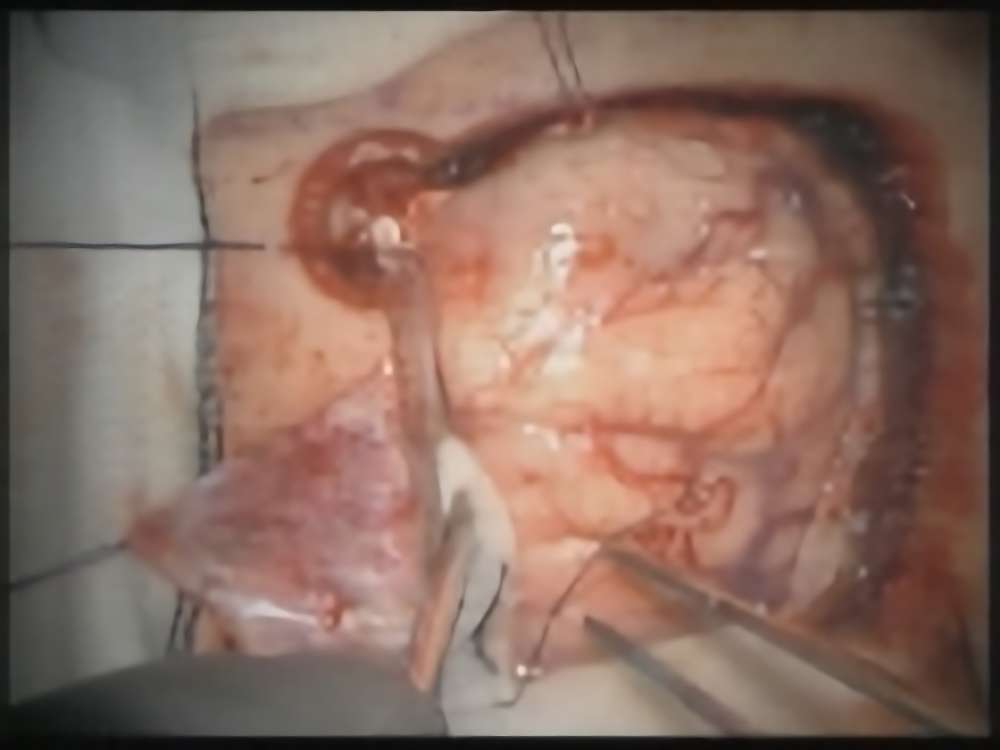

術中写真

摘出 前

摘出 中

摘出 後